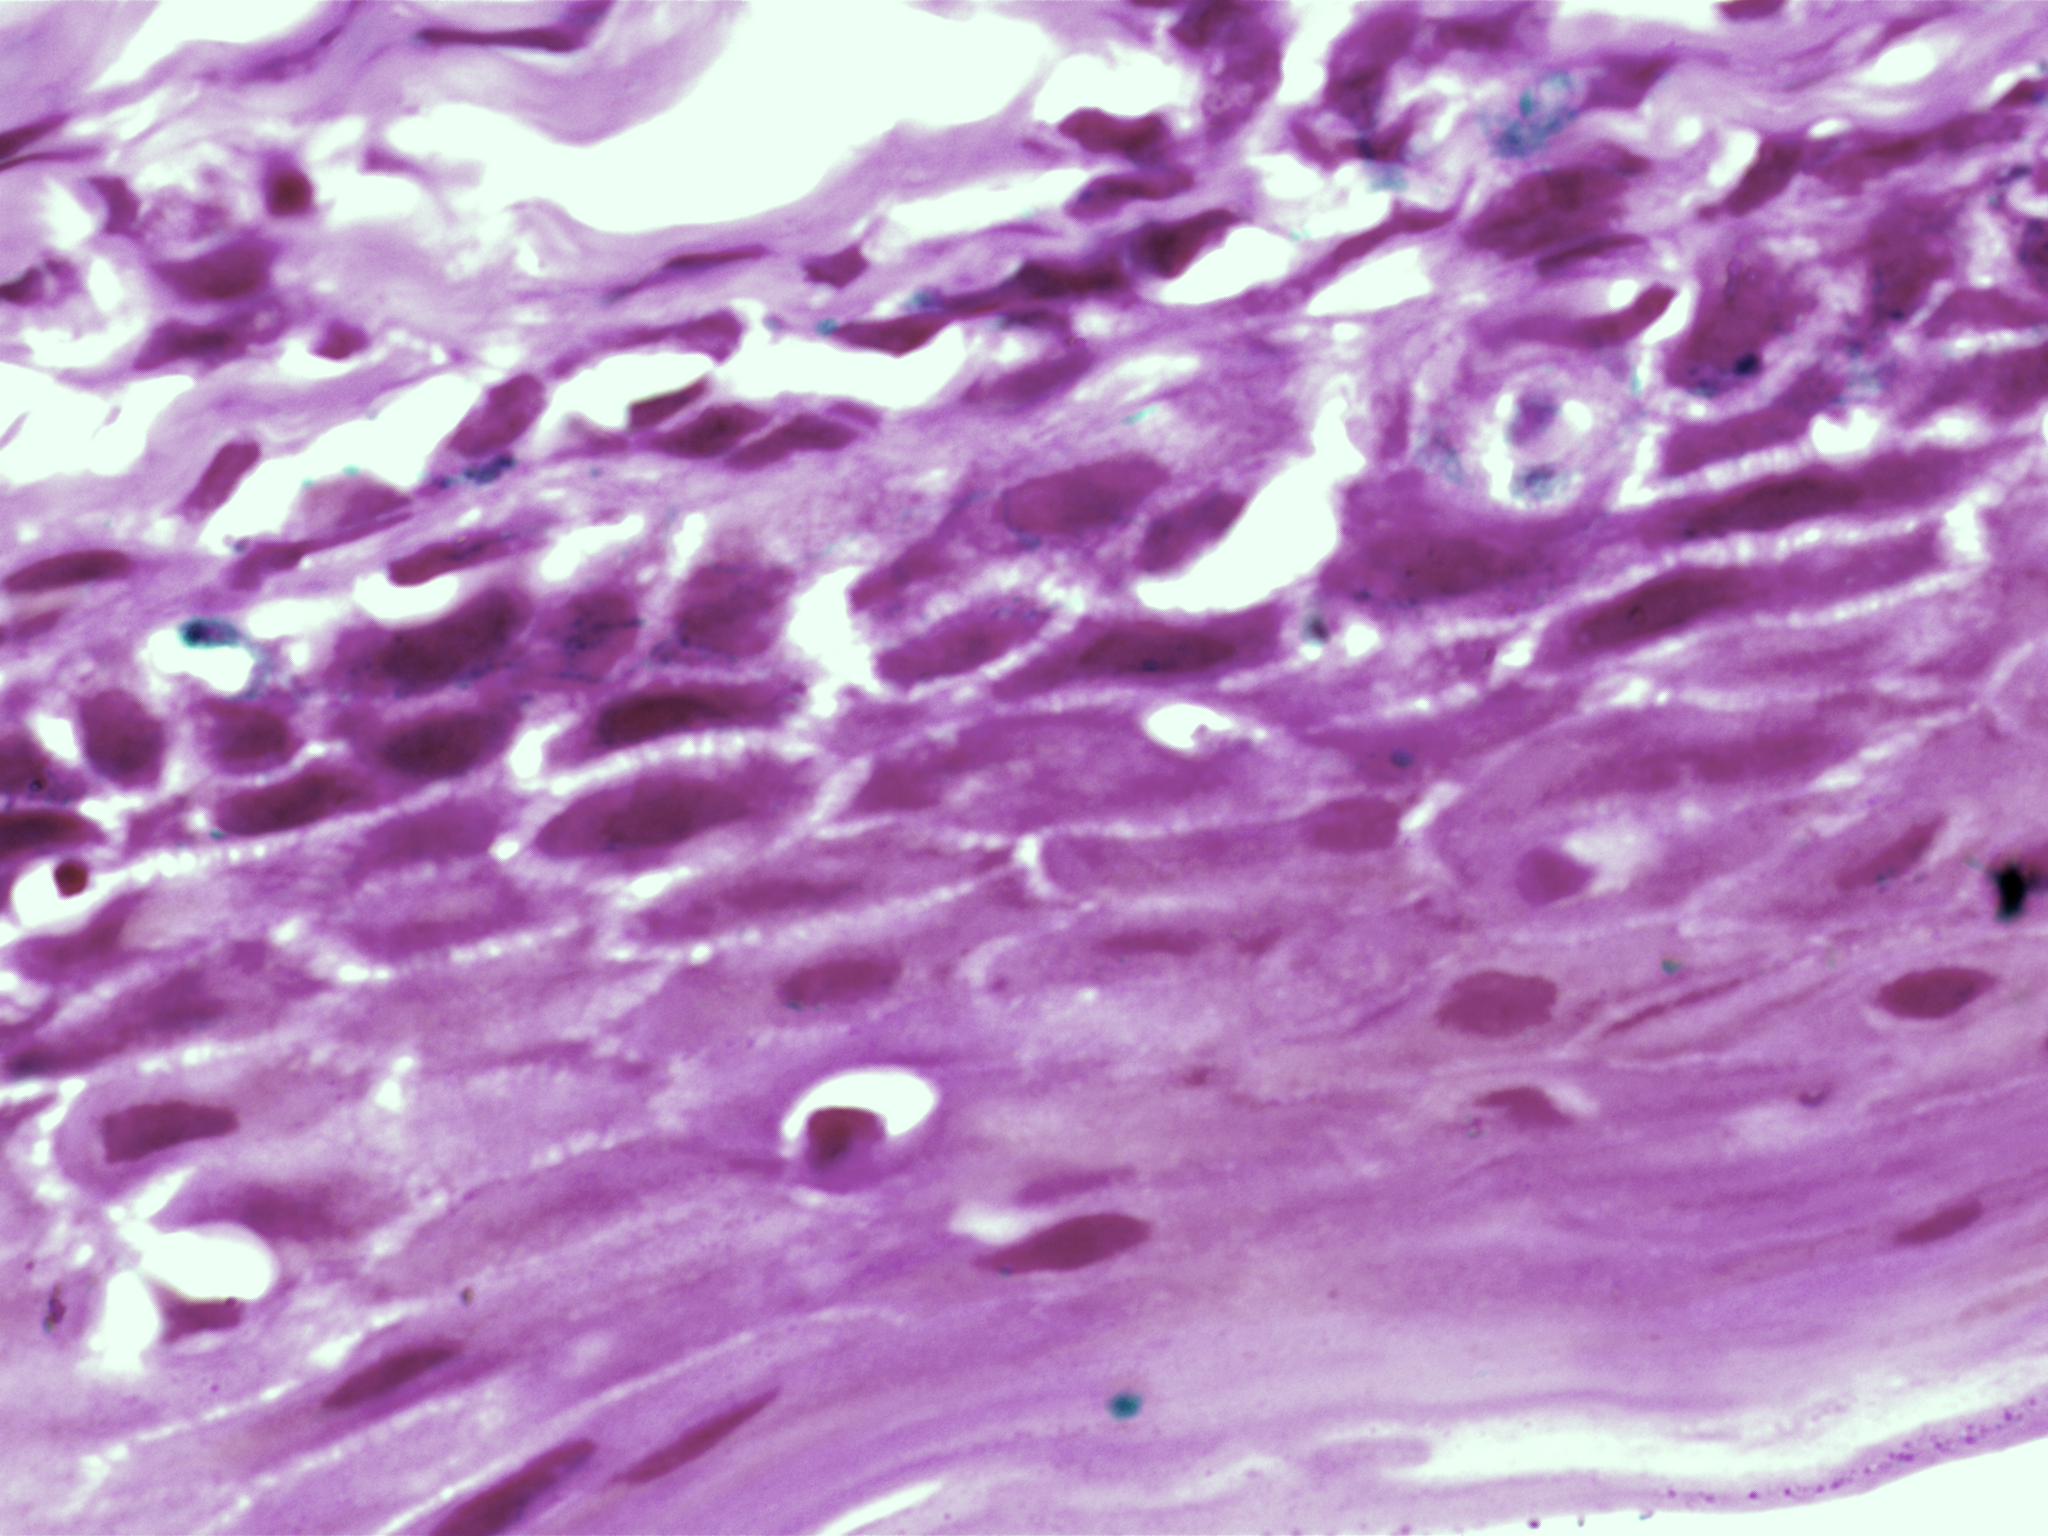

| Title: | High-resolution AI image dataset for diagnosing oral submucous fibrosis and squamous cell carcinoma |

| Description: | Oral cancer is a global health challenge with a difficult histopathological diagnosis. The accurate histopathological interpretation of oral cancer tissue samples remains difficult. However, early diagnosis is very challenging due to a lack of experienced pathologists and inter- observer variability in diagnosis. The application of artificial intelligence (deep learning algorithms) for oral cancer histology images is very promising for rapid diagnosis. However, it requires a quality annotated dataset to build AI models. We present ORCHID (ORal Cancer Histology Image Database), a specialized database generated to advance research in AI-based histology image analytics of oral cancer and precancer. The ORCHID database is an extensive multicenter collection of high-resolution images captured at 1000X effective magnification (100X objective lens), encapsulating various oral cancer and precancer categories, such as oral submucous fibrosis (OSMF) and oral squamous cell carcinoma (OSCC). Additionally, it also contains grade-level sub-classifications for OSCC, such as well- differentiated (WD), moderately-differentiated (MD), and poorly-differentiated (PD). The database seeks to aid in developing innovative artificial intelligence-based rapid diagnostics for OSMF and OSCC, along with subtypes. |

| Imaging Type: | Histopathology (HISTO) |

| Imaging Sub-type: | Diagnostic Pathology |

| The ORCHID database is an extensive multicenter collection of high-resolution images captured at 1000X effective magnification (100X objective lens). Tissue slides were collected with the approval of an ethical committee from the participating hospitals and research institutions. The buccal mucosa tissue samples were collected for three classes, normal, OSMF, and OSCC, with grade-wise annotation from the pathologists at each hospital. Biopsy samples of normal, OSMF and OSCC tissues underwent H&E staining. The staining procedure was conducted either in-house or outsourced to different laboratories. To eliminate staining variations across different laboratories, the preparation of H&E slides involved five histopathology labs, each utilizing their own independently developed and optimized protocols for the staining process. Following staining, the samples were examined under a microscope by a skilled histopathologist to assess cellular morphology, and tissue architecture, and identify any distinctive features or abnormalities specific to each sample type. This evaluation by the histopathologist involved grading the tissue slides for OSCC and OSMF, as well as differentiating between normal and diseased tissue sections. Images were acquired using a 1000X magnification (100X objective) lens from Leedz microimaging (LMI) bright field microscopy. To capture the images consistently, we utilized ToupView imaging software, which was configured for automatic adjustments. This setting applies to both white balance and camera settings, thereby standardizing the image acquisition process across different slides. The images of the H&E stained slides were captured at 1000X magnification(100X objective lens). By setting the ToupView software to automatically adjust white balance and camera settings, we aimed to minimize human intervention and the variability it introduces. This approach ensures that the images are not only consistent but also replicable in different laboratory settings, provided similar equipment and software settings are used. We collected approximately 100–150 images per tissue slide, which were stored in PNG file format. |